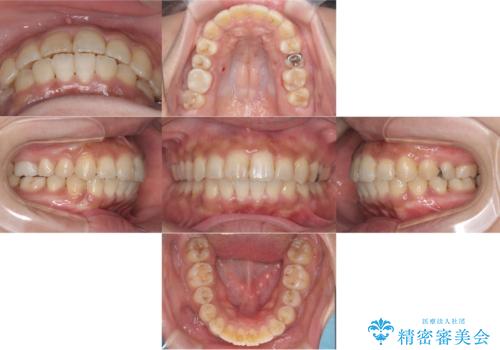

[マウスピース矯正] がたがたの歯並びをきれいにしたい

![[マウスピース矯正] がたがたの歯並びをきれいにしたいの症例 治療前](https://seimitsushinbi.jp/wp/wp-content/uploads/2025/06/0d238550c8a0fddc4de7b2c337c6c786-500x350.jpg?v=1750323380)

![[マウスピース矯正] がたがたの歯並びをきれいにしたいの症例 治療後](https://seimitsushinbi.jp/wp/wp-content/uploads/2025/06/IMG_0002-2-500x350.jpg?v=1750323305)